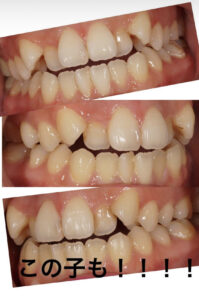

次の方を見てください。

他院で、もうそろそろ終了する裏側矯正の方です。

口元どうなってますか?

出てませんか?口元。

下の唇のほうが出ているかもしれません。

顎に梅干しのようなシワができているのは

お口を閉じにくい証拠です。

この方のスタートのお顔がわからないのでなんとも言えませんが

歯は並んでいました。

ただし口元が出たことで

鼻は低いことになったでしょう。

歯も長くなったでしょう。

ここまで治療がすすめば再治療は困難です。